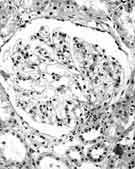

肾穿病理结果 光镜:全片共32个肾小球,6个球性硬化,余肾小球细胞数未见明显增多,球囊腔普遍增宽,大部分肾小球体积增大,可见节段性系膜细胞增生和系膜基质增多。毛细血管开放良好,肾小球基底膜(GBM)未见明显增厚,部分肾小球旁器肥大(图1,图2),可见入球小动脉壁增厚及玻璃样变。部分肾小管上皮细胞可见浊肿及气球样变性,可见小灶性肾小管基底膜(TBM)增厚及小管萎缩,肾间质内小叶间动脉壁增厚及玻璃样变。免疫荧光:全部阴性。

图2 肾小球囊腔增宽,肾小管上皮细胞可见浊肿及气球样变性(PAS,×400)